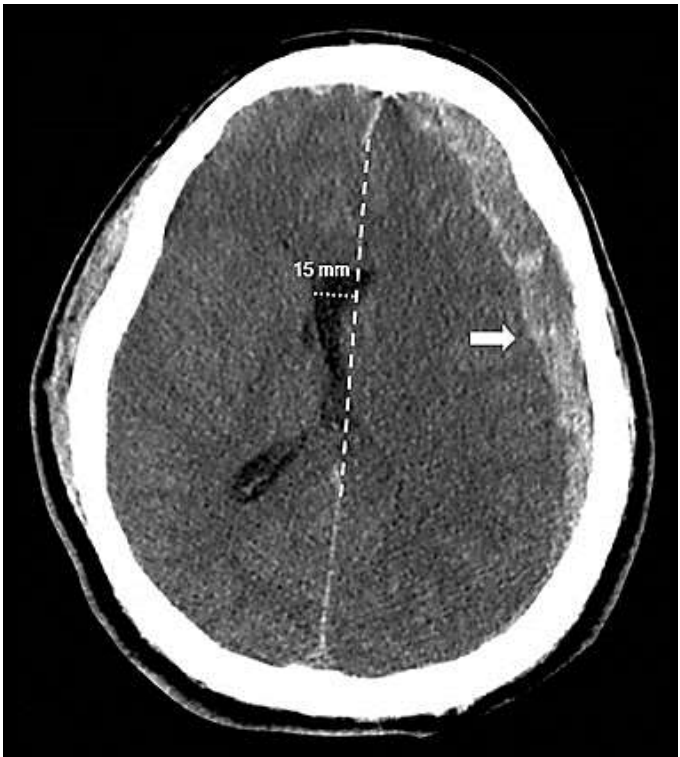

Homem de 75 anos, vítima de queda de 3 metros de altura, seguida de perda de consciência, vômitos e cefaleia. Chega à emergência apresentando-se: sonolento, expressando sons incompreensíveis, respondendo a estímulos verbais (abre o olho quando contactado) e localiza a dor. Pupilas anisocóricas, SO2: 85%, PA: 110 x 75 mmHg.

Sobre o caso anterior, o paciente encaminhado para realização de tomografia de crânio (imagem).

Tomografia de crânio